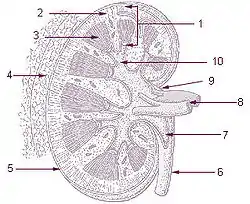

Frontal section through the kidney Vertical section of kidney. (Label "medullary sub." visible near top.)